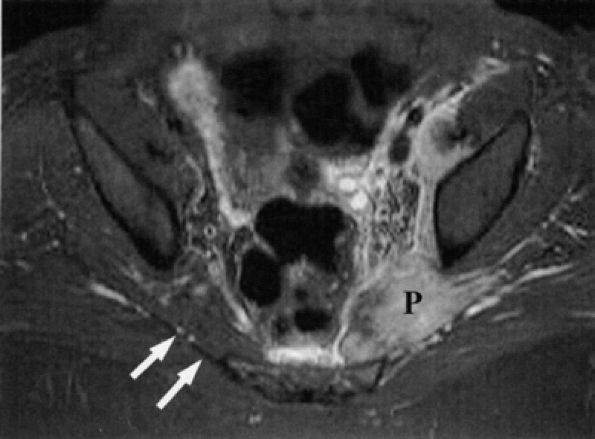

|

FIGURE 6.22 ● Femoral neuropathy secondary to sports-related iliacus muscle tear. Axial T1-weighted image demonstrating enlargement of the left iliac (white asterisk) and psoas muscles (black asterisk). The anteriorly displaced femoral nerve is not visualized. Compare with the right normal iliac (I) and psoas (P) muscles.